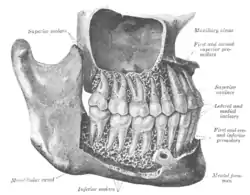

![]() The permanent teeth, viewed from the right. The external layer of bone has been partly removed and the maxillary sinus has been opened. | |